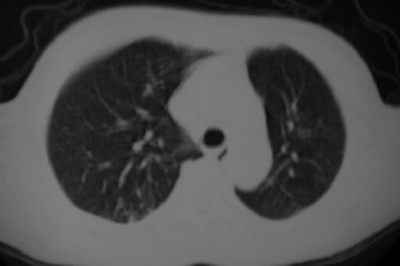

以下是引用liuyue在2007-4-10 7:56:00的发言:[br]周围型肺癌侵犯肋骨,左肺转移。

以下是引用zhangzhongshou在2007-4-10 10:24:00的发言:[br]右肺下叶背段厚壁空洞,伴胸膜改变、肋骨破坏,其内可见死骨、周围骨质硬化,左肺可见小结节影,[br]单纯影像学更支持结核。建议进一步检查。